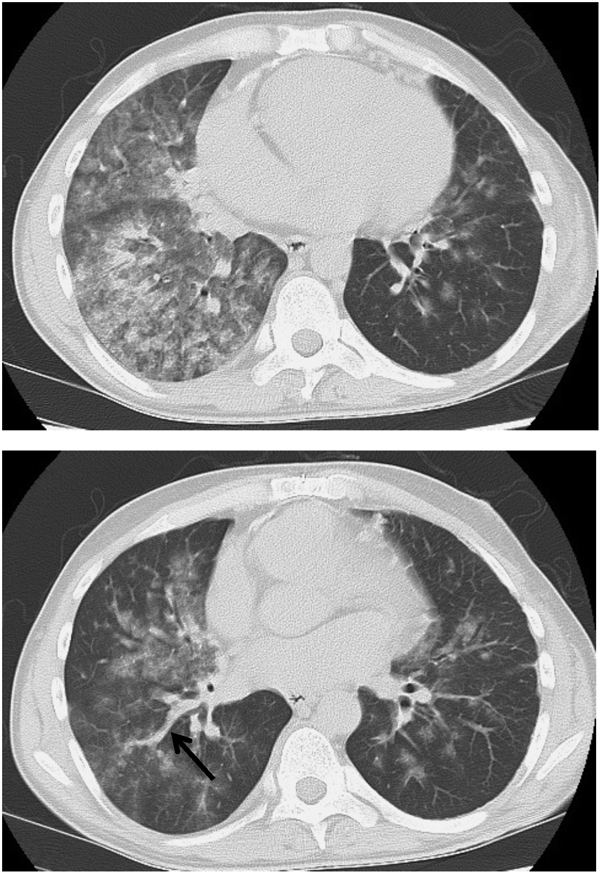

6)肺血管障害

喀血・肺出血は,成人期には比較的多く認められ,本邦でも18歳以上(18~56歳)253例中41例(16%)と報告されている5).アイゼンメンゲル症候群に限ると18歳以上(18~69歳)77例中36例(47%)と高率になる6)

下気道感染を契機とすることが多く,時に致命的となる.肺動脈瘤破裂,肺塞栓,体肺側副血行路,肺内新生血管,肺動静脈瘻などの肺血管の異常と,出血傾向が原因である(図6).

Pediatric Cardiology and Cardiac Surgery 31(3): 95-101 (2015)

図6 左下肺野の広範な肺出血と,出欠の原因となった肺動静脈瘻により拡張した肺静脈を認める(矢印)

気管支鏡ではさらなる出血の危険を伴う.急性期治療では,止血剤,血液製剤,ビタミンKの他に,重症例では第Ⅷ因子誘導薬のデスモプレシンが有効な場合がある.肺出血をはじめとして致命的な出血性疾患の合併が多いため,チアノーゼ性心疾患に対して,血栓症予防のための抗血小板薬や抗凝固薬の使用は慎重に行う必要がある.